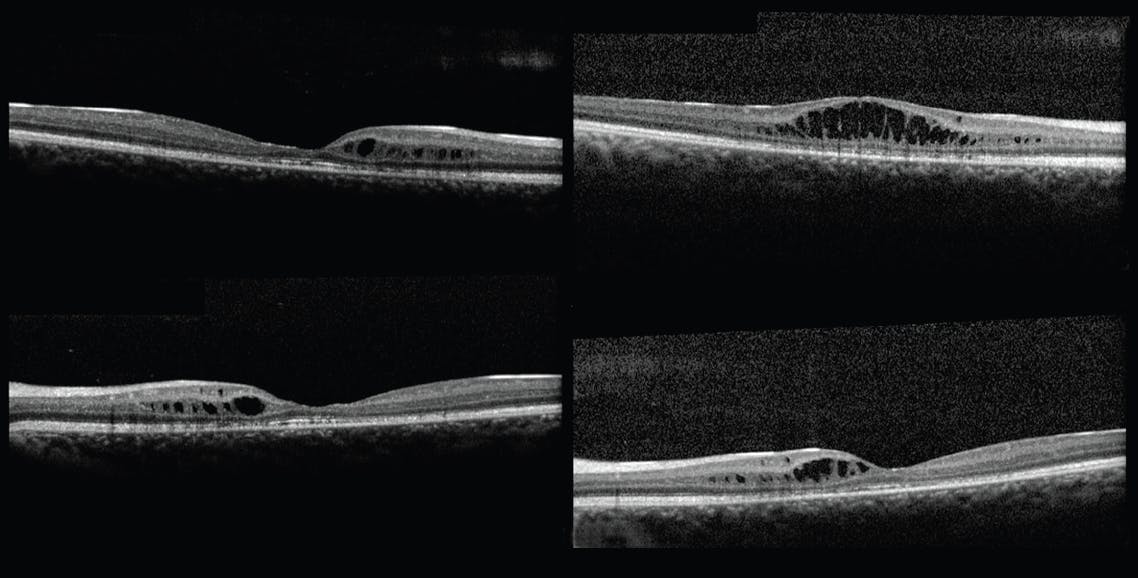

OCT showed foveal retinoschisis between the inner nuclear layer and outer plexiform layer, which was confined to the perifoveal space (Main Figure 2). His peripheral visual field was normal. A negative electroretinography result confirmed the diagnosis of juvenile X-linked retinoschisis (XLRS), and genetic testing revealed the XLRS1 pathogenic variant. The patient’s brother was examined without any evidence of XLRS.

The Mizuo-Nakamura phenomenon did not appear at the 1-year follow-up. At this time, OCT revealed the progression of retinoschisis, spreading to a wider area and to the right fovea (Figure 3), accompanied by worsening BCVA (20/70 OD). He has been followed annually and demonstrates stable BCVA (20/70 OD and 20/50 OS) and retinal findings.